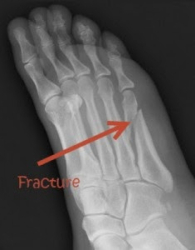

Диуретичните свойства на кофеина започват да действат и всички минерали, включително магнезий, калций и цинк, предназначени за костите, се изхвърлят с урината.